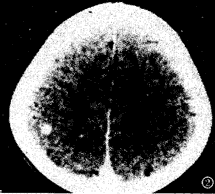

图1 右顶叶多结节病灶(不规则形强化),病灶周围水肿( 治疗前)。

图2 为图1病人治疗后,病灶呈小结节状强化,周围水肿消失。